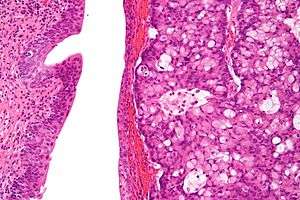

| Micrograph of urachal carcinoma (right of image) and non-malignant urothelium (left of image). H&E stain. | |

Urachal cancer usually is an adenocarcinoma (about 90%) mostly with mucinous/colloidal histology. The histology can be difficult to distinguish especially from colorectal cancer and primary adenocarcinoma of the urinary bladder. Immunohistochemistry in this situation is of little help with stains for betaCatenin and Cytokeratin 7 can be helpful. Other rare types include urothelial carcinoma, squamous cell carcinoma, neuroendocrine carcinoma and sarcoma.[2][4][8]